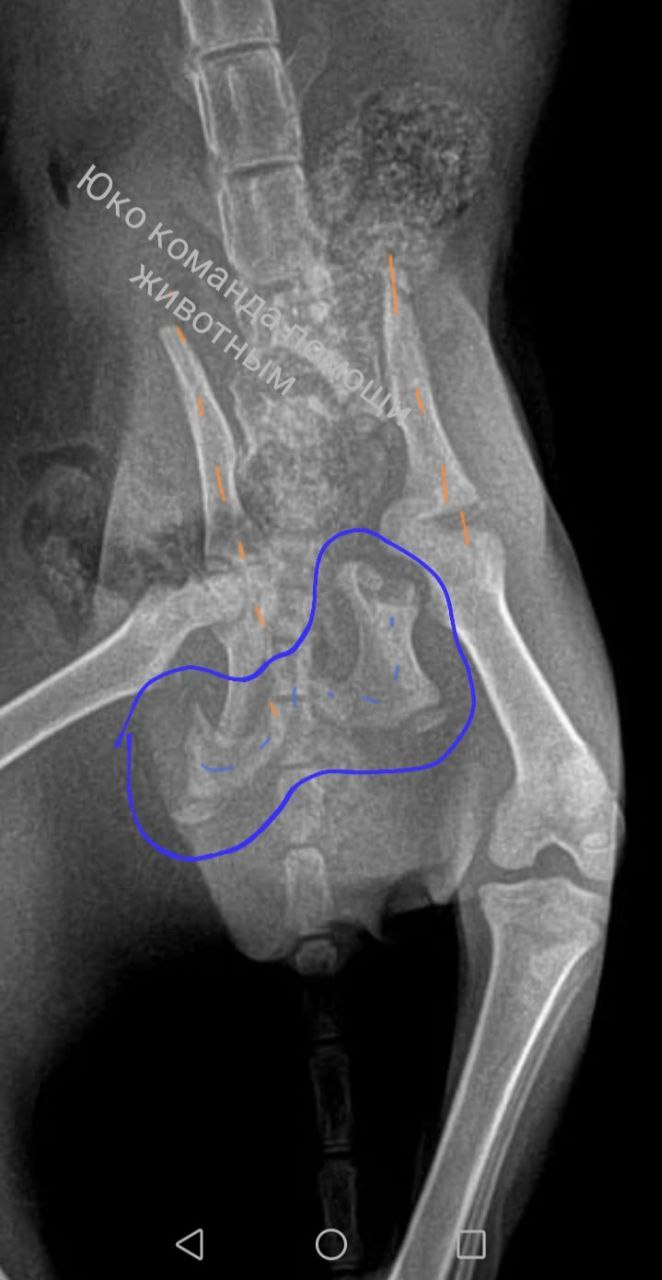

Первый рентген

К сожалению, на рентгене не пузико, а грыжа.

Осколок тазовой кости пробил брюшную полость, потому прямой кишечник выпал под кожу, пережался, движение масс после пережатого места остановилось.

А это интоксикация и потенциальный некроз, возможный перитонит и в целом малооптимистичная картина.

А отсюда осколки

У Бусины оказалась отломана и смещена вся нижняя часть таза.

К сожалению, такие травмы у котят неоперабельны.

Котенку три месяца, она растет, кости тоже растут. Жесткую конструкцию нельзя, перелом уже несвежий..

"Срастется как срастется" констатировала врач и забрала мелкую на операцию по ушиванию грыжи.

К слову, травма эта не высотная. То есть кошка не упала из окна. Ее вполне вероятно либо сбили либо переехали на чем-то либо причинили увечье целенаправленно. В таком состоянии она ползала около недели.